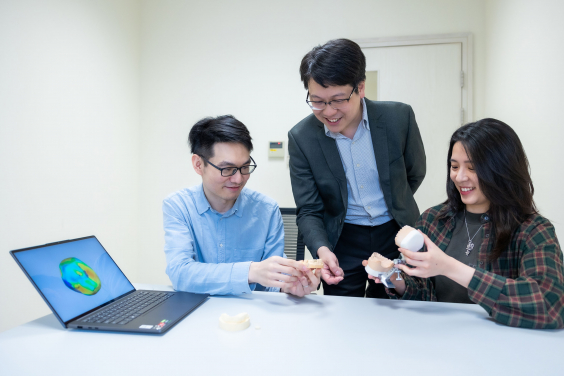

Project co-investigator Dr Hao Ding and the design of a personalised tooth crown using generative AI.

The team, led by Dr James Tsoi, Associate Professor in Dental Materials Science collaborated with colleagues from HKU Faculty of Engineering’s Department of Computer Science to take a leap forward for the next-generation AI-designed dental prosthesis production workflow.

“We used a 3D-DCGAN (3D-Deep Convolutional Generative Adversarial Network) approach to ‘teach’ the AI algorithm ‘good’ designs by feeding the algorithm with over 600 cases of natural and healthy dentition. The algorithm improves the quality of the design through internal competition between a generator and a discriminator,” said Dr Hao Ding, a co-investigator on the project.

“During the training process, natural teeth morphological features were learned by the algorithm, so that it can design dental crowns comparable to a natural tooth — both morphologically and functionally.” Dr Ding added.